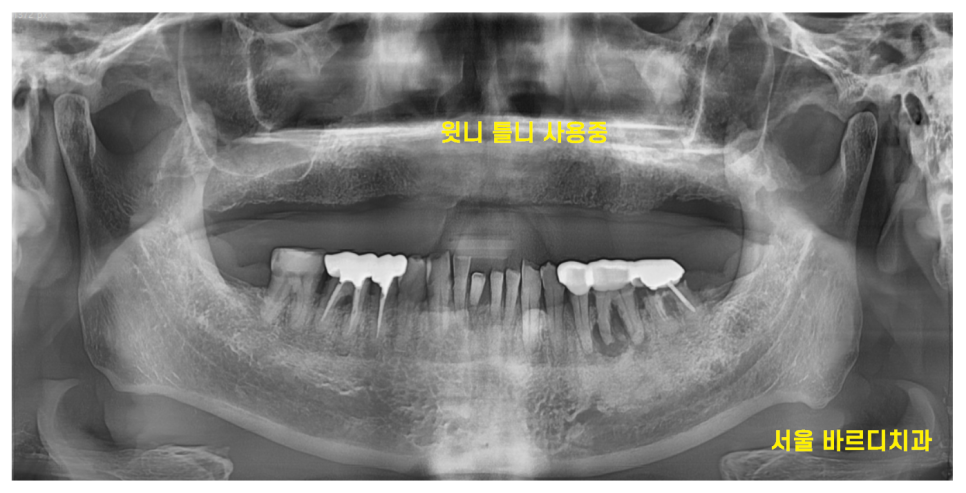

닳아버린 치아와

위에의 경우 모두 빠져버려서

세월의 흐름을 실감했습니다.

요즘은 거의 쓰이지 않는 은니

(그만큼 하신지 오래됐다는 거겠지요 ㅎㅎ)

오래 쓰신 위에 틀니도 둔촌동 치과에서 새로 만들었고요.